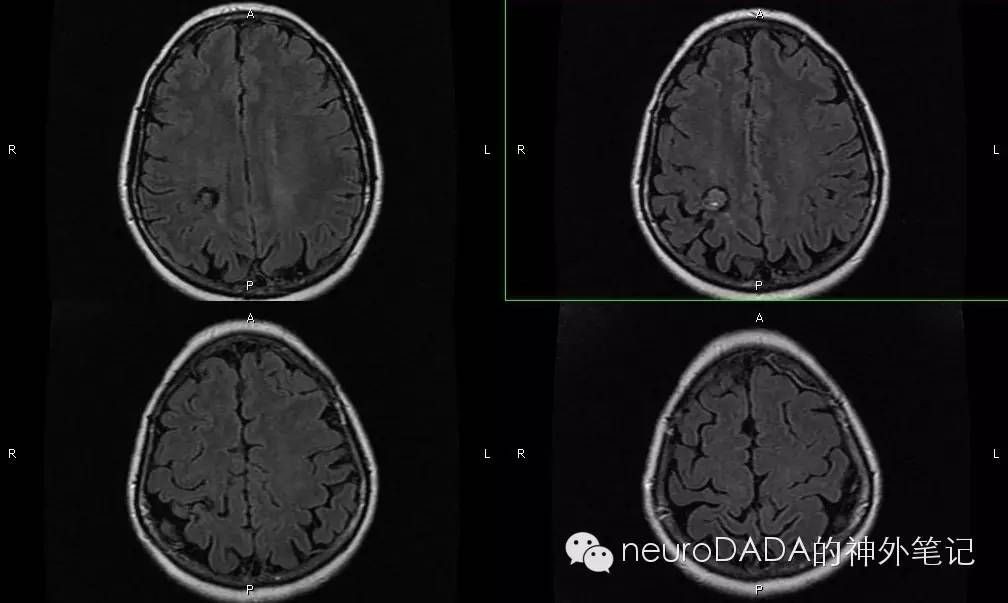

术前MRI-水平位提示:前后方向病变位于中央后沟,内外方向位于半卵圆中心的外侧,高度位于顶间沟水平;该患者右侧脑沟特别明显,病变恰位于中央后沟与顶间沟交汇处,因此只需沿着脑沟进入,而无需切开皮层,寻找含铁血黄素沉着即可

术前MRI-T1矢状位提示:病变高度位于胼胝体上缘,前后位于中央后沟、即侧脑室体部与房部的交界处。

这是术前做的体表定位,我用到了两套方法:根据影像量尺寸、解剖投影定位。此例发现并不吻合,原因后面会说。

方法一,先看根据影像量尺寸的定位:在矢状位的中线层面,根据冠状缝或枕外粗隆来确定前后方向的位置;再根据水平位病变距离耳眦线的层面数来确定上下位置,这个十字交叉处的圆形即为根据此法作出的定位,并以此为中心作一马蹄形皮瓣切口(初出是茅庐实在没有底气,于是作了这么大一个切口。。。请勿吐槽)。

方法二,再看根据解剖投影的定位:先把各个基线画好,侧裂与颞上线之间为额下回-侧脑室额角,颞上线对应额下沟-侧脑室顶壁-胼胝体下缘,中央沟则可确定中央后回-中央后沟的大致位置,结合侧裂又可确定缘上回-顶间沟的大致位置。根据术前的读片,病变就位于中央后沟和顶间沟相交的这个深沟内,而这个深沟应该位于途中切口的后方拐角附近。

两套方法不相吻合,选哪个。。。当时还是对自己的解剖定位没有信心,于是选择了方法一。。。果然,打开硬膜,深深的中央后沟和顶间沟就在骨窗的后上边缘了,还好骨窗做足了,至少看到了这脑沟,我也算送了口气。。。接下来的经脑沟入路海绵状血管瘤切除术就交给老板了。。。